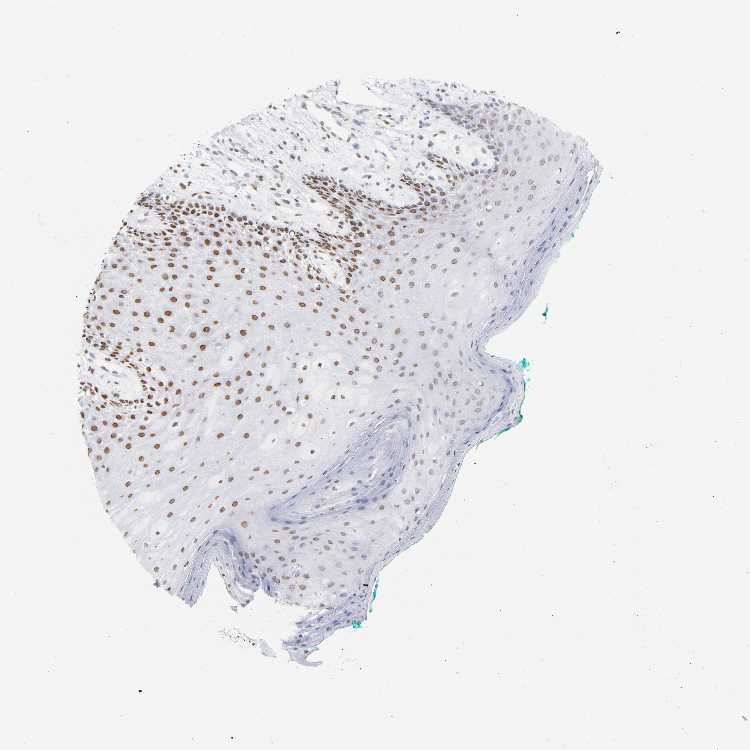

TISSUE PRIMARY DATA ORAL MUCOSA Show tissue menu

ORAL MUCOSA - Antibody stainingi

Antibody staining in the annotated cell types in the current human tissue is reported as not detected, low, medium, or high, based on conventional immunohistochemistry profiling in selected tissues. This score is based on the combination of the staining intensity and fraction of stained cells.

Each image is clickable and will lead to virtual microscopy that enables deeper exploration of all samples and also displays staining intensity scores, fraction scores and subcellular localization as well as patient and tissue information for each sample.

Antibody HPA047549Antibody HPA062226Antibody CAB004254

Squamous epithelial cells Not detectedHighHigh